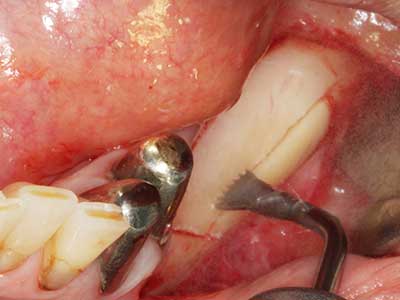

Si es preciso realizar intervenciones quirúrgicas en las que el hueso está en contacto directo con estructuras sensibles, como son los vasos sanguíneos o los nervios, los instrumentos rotativos presentan un enorme potencial de provocar lesiones iatrogénicas. Así, precisamente en la representación de nervios después de una lesión iatrogénica, o en el transcurso de la lateralización de un nervio para resecciones, reconstrucciones o incorporación de implantes, los equipos piezoeléctricos pueden resultar muy útiles para preparar la tapa ósea y retirar las partes de tejido duro cercanas al nervio (fig. 17-20). Por lo general, un ligero contacto del cordón nervioso con el inserto piezoeléctrico no tiene consecuencia alguna; ahora bien, un procedimiento poco cuidadoso con movimientos tipo sierra o piezas de trabajo sobre la base ósea aún existente puede provocar lesiones nerviosas temporales o incluso permanentes. Con todo, el riesgo de sufrir una lesión de este tipo se considera significativamente inferior que en los casos en los que se utilizan sierras y fresas (Pereira, Gealh et al. 2014).

Fig. 18: Preparación de una tapa cortical con la sierra ósea piezoeléctrica (Piezomed, W&H).

Fig. 19: Zona operada después de neurolisis y eliminación del osteomo.

Fig. 20: La tapa ósea extraída se readapta y se fija mediante un tornillo para osteosíntesis (KLS Martin, Tuttlingen).